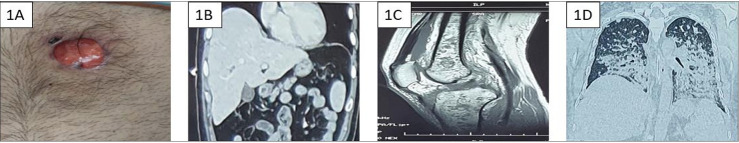

Methods: We describe the case of a 33-year-old male with uncontrolled diabetes mellitus who initially presented with a skin lesion, which was followed by gradual multiorgan involvement diagnosed as melioidosis based on culture-positive results from blood and synovial fluid, and needed ICU admission.

Results: He was successfully treated with intravenous antibiotics and invasive mechanical ventilation after ICU admission.

Conclusion: Cutaneous melioidosis can lead to ICU admission and, if untreated, has a high fatality rate. Faster diagnostic methods like VITEK 2 Compact and MALDI TOF substantially reduce delays in initiating required treatment.